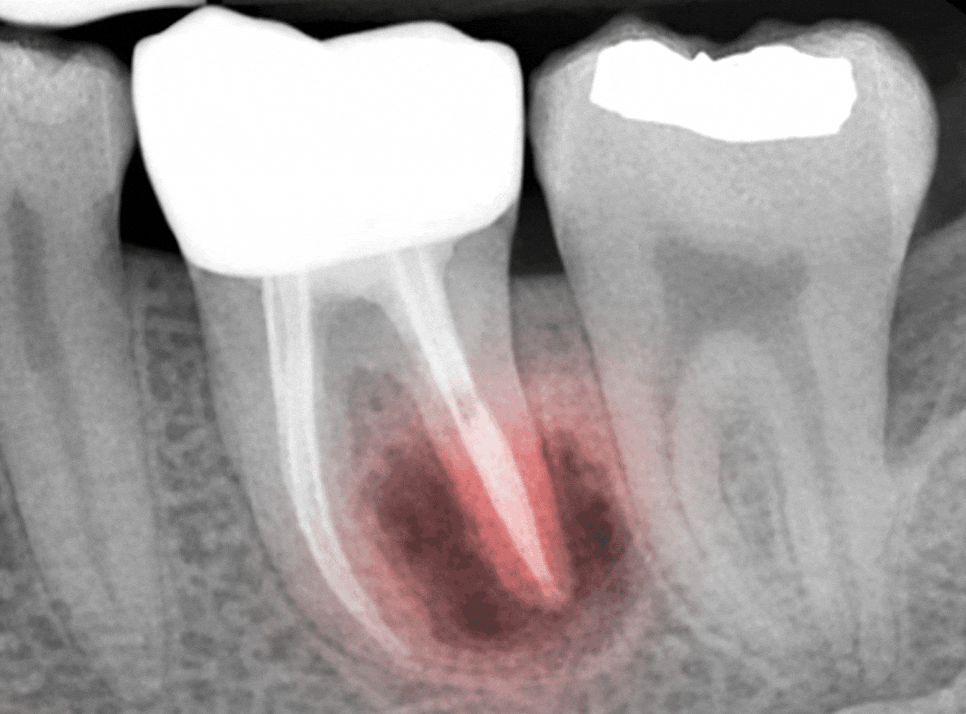

그 다음에는 놓쳤던 근관을 찾는 과정으로

선유도 치과 는 미세현미경을 사용해

육안으로는 보이지 않는 작은 미세관까지

모두 찾아내는 과정이 중요하다 생각합니다.

근관을 모두 찾았다면 염증을 일으킨 세균을

완전히 제거하는 과정으로 넘어갑니다.

소독이 완료되면 생체친화적인 재료로

빈 공간이 없도록 충전하여 완전히 밀봉합니다.